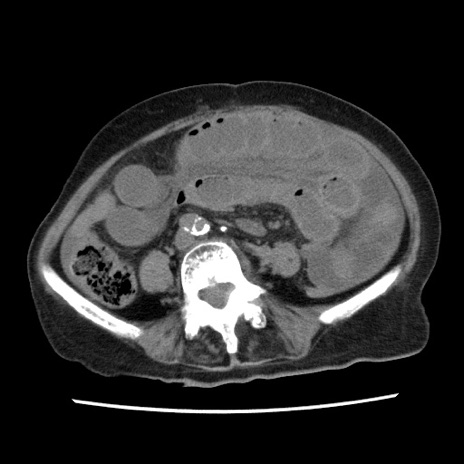

症例1(横断像)

【症例】80歳代女性

【主訴】腹痛

【現病歴】8時間前から腹痛あり来院。

【既往歴】糖尿病、脂質異常症、子宮体癌にて子宮全摘術

【身体所見】意識清明・会話良好だが腹痛で苦悶様、全腹部にわたって反跳痛と圧痛あり

【データ】WBC 13600、CRP 0.14、LDH 224、CK 90